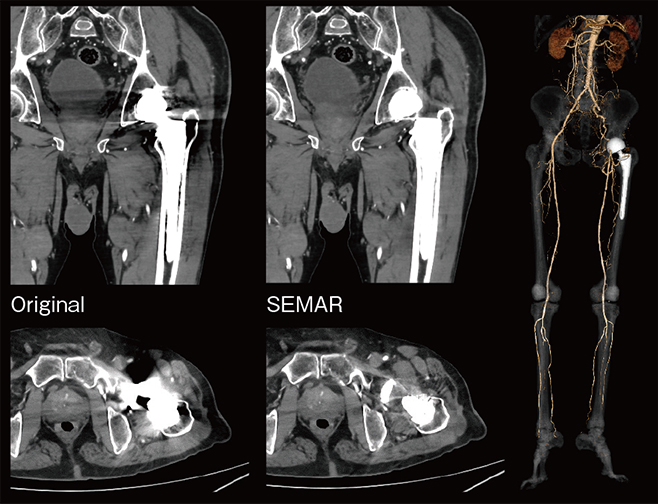

Aquilion Serveの導入後、CT検査は月間約160件と以前に比べて1割程度増加している。村上放射線科部長は、「画質の向上と低被ばくで検査が可能になったことで、依頼件数が増加しています」と言う。Aquilion ServeではAiCE-iによって被ばく線量が低減されており、冠動脈や胸部でDRLs2020の半分、腹部や胸腹部では1~2割減で検査を行っている。また、下肢動脈造影検査では、撮影スピードの向上によって広範囲を短時間で撮影できることから、造影剤量を従来の2~3割程度削減できた。さらにAquilion Serveでは、金属アーチファクト低減技術の「SEMAR(Single Energy Metal Artifact Reduction)」も利用できる。SEMARの運用について村上放射線科部長は、「人工骨頭のアーチファクトが除去されて下肢動脈が明瞭に描出され、診断が可能な画像が提供できています」と述べる。